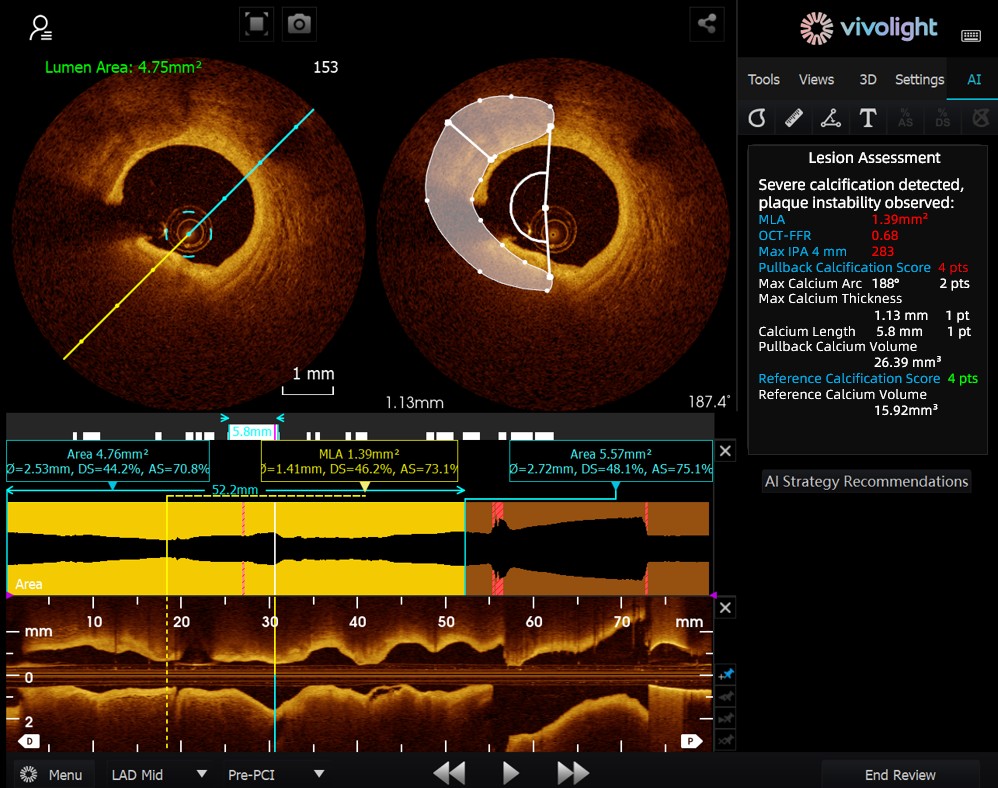

Développé à partir du système OCT de Vivolight Medical, l'AI-OCT est un système d'aide à la décision intelligent de nouvelle génération pour l'imagerie intravasculaire. Il intègre des données diagnostiques d'imagerie intravasculaire dispersées — notamment le diamètre de la lumière, les lésions responsables, l'OCT-FFR et la nature des plaques — afin d'élaborer des stratégies de traitement complètes et des recommandations concrètes. Logiciel de recherche indépendant intégré à la plateforme OCT, il est co-développé avec différents hôpitaux pour créer des versions personnalisées adaptées à des besoins cliniques spécifiques.

Lors de ce forum de pointe, les experts ont souligné que le système AI-OCT représente une transformation majeure, passant de la simple « visualisation d'images » à l'« élaboration de plans de traitement ». Il permet de relever les défis posés par la surcharge d'informations et la complexité des décisions à prendre lors des interventions cardiaques, qui reposent traditionnellement sur l'expérience du médecin. Les principaux avantages de ce système sont les suivants :

●Guidage peropératoire en temps réel : Il organise dynamiquement les informations diagnostiques pendant l'intervention chirurgicale, en fournissant des indicateurs clés et des recommandations cliniques.

Le système AI-OCT adopte une architecture « petit modèle + données massives + grand modèle » : les petits modèles permettent une interprétation précise des images, tandis que les grands modèles sous-tendent un raisonnement clinique complet. S’appuyant sur des bases de données cardiovasculaires de haute qualité et la technologie RAG (Retrieval-Augmented Generation), il offre une prise en charge globale, de l’évaluation des lésions à l’élaboration de la stratégie de traitement.